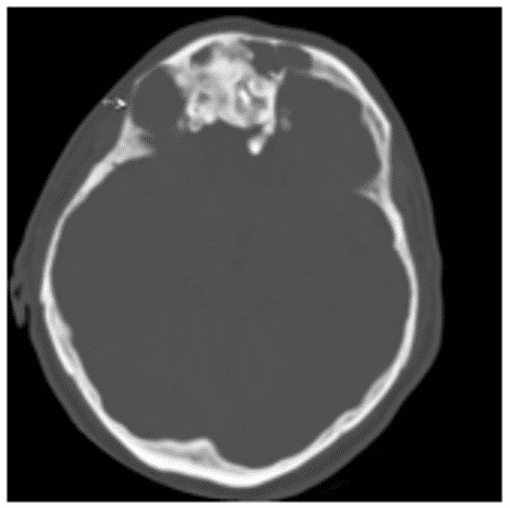

Остеобластома на КТ обычно представлена сочетанием плотной кости и участков затемнения (рисунок 4).

Рис. 4. КТ черепа, аксиальная плоскость. Гигантская остеобластома, распространяющаяся в правую орбиту, полость носа и переднюю черепную ямку

Данные КТ позволяют определить признаки локально агрессивного роста остебластомы, место ее исходного роста, наличие/отсутствие распространения опухоли за пределы околоносовых пазух.